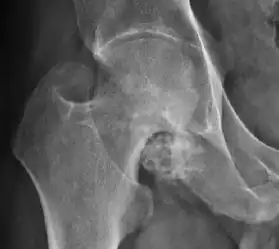

There are other pathological conditions that can affect the hip joint and radiographs help to make the appropriate diagnosis. Acute bacterial septic arthritis can be diagnosed by radiographs when a fast regional osteoporosis and destructive monoarticular process develops (Figure 1(f)). In case of tuberculous or brucella arthritis it is manifested as a slow progressive process, and diagnosis may be delayed.[1]

Synovial chondromatosis can be confidently diagnosed by X-ray when calcified cartilaginous chondromas are seen. However, other synovial proliferative processes, such as pigmented villonodular synovitis, require MRI for accurate diagnosis, although noncalcified synovitis can be suspected in radiographs by indirect signs, such as soft tissue swelling and/or erosions in the femoral head, femoral neck, or acetabulum (Figure 7).[1]

Figure 7:

Axial CT image of pigmented villonodular synovitis eroding the posterior cortex of the femoral neck.[1]

Sagittal T2* gradient echo image showing a posterior soft tissue mass with hypointense areas secondary to hemosiderin deposition.[1]

X-ray of synovial chondromatosis.[1]

CT of synovial chondromatosis.[1]